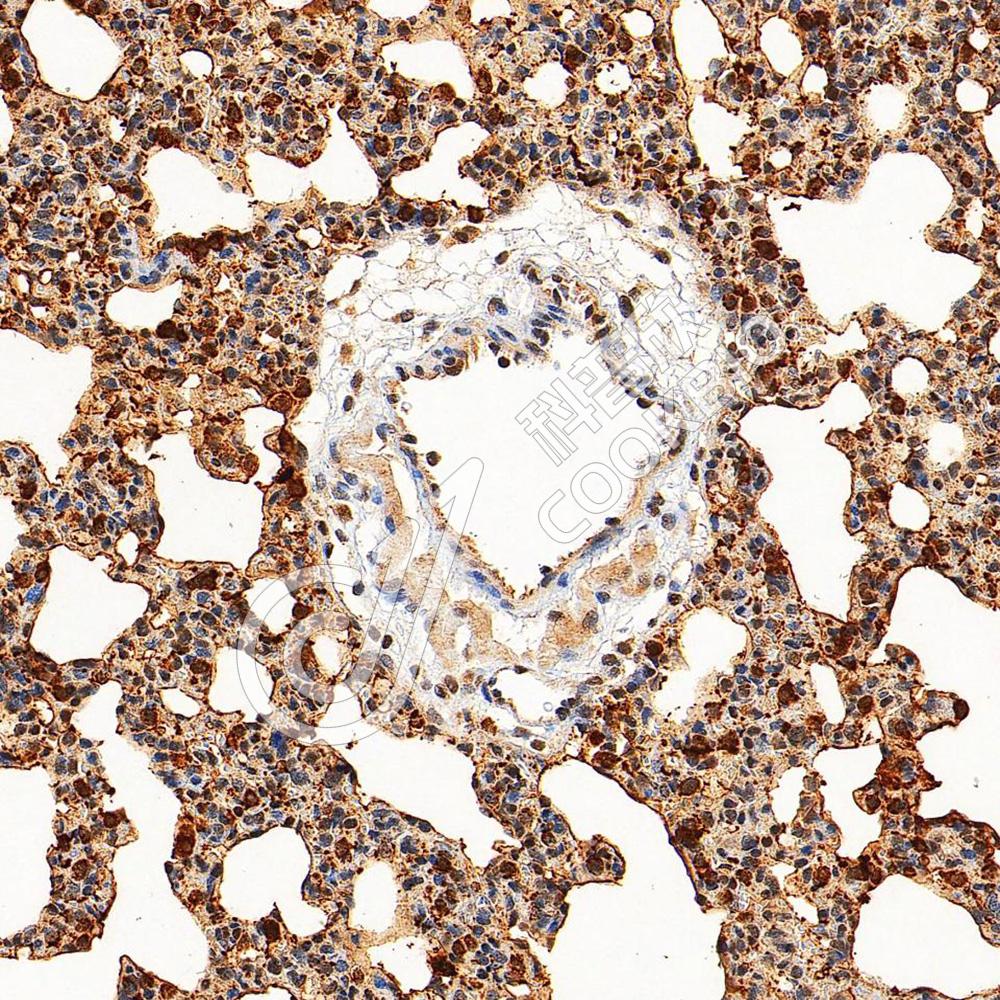

IHC检测SFTPA1蛋白(货号 K1342495).

样品: 小鼠肺, 4%多聚甲醛 (货号KSG1101) 固定12-24小时.

抗原修复: 柠檬酸抗原修复液(干粉, pH 6.0) (KSG1201), 98℃, 20分钟.

—抗: 1: 1500稀释, 4℃ 孵育过夜.

二抗: S-vision免疫组化多聚二抗(山羊抗兔),即用型 (货号KB3906), 室温孵育20分钟.